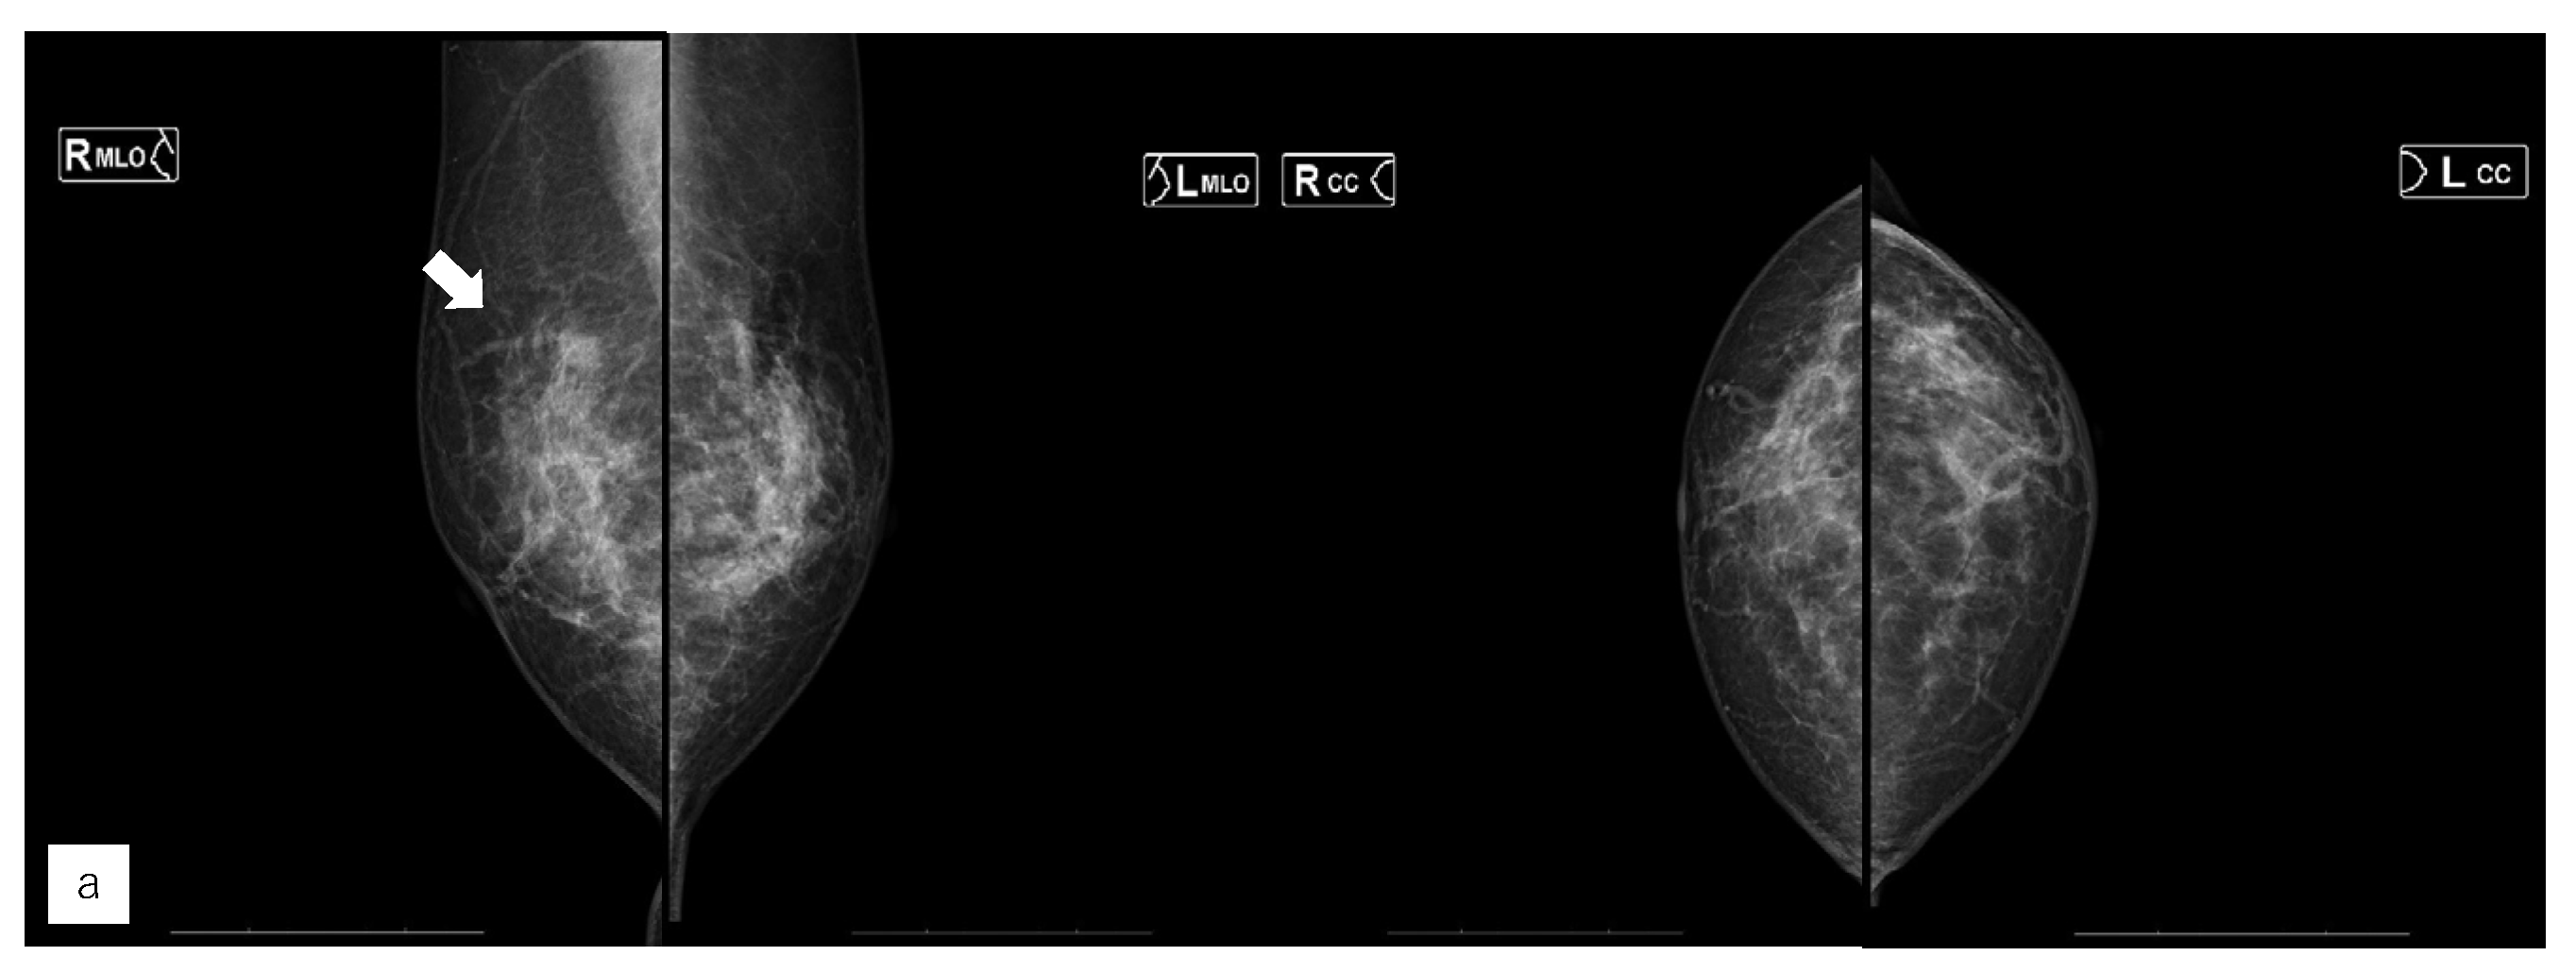

Figure 5. Representative case (case 7). (a) MG. (b) US. (c) MRI. (d) AI diagnosis.A 63 yearsold woman had left side breast cancer. Two years later, she was diagnosed with right breast cancer. It was T1c, triple negative breast cancer. (a) A mass was found in the right upper area in mammography (MG) and diagnosed as breast imaging reporting and data system (BI-RADS) Category 4. (b) Ultrasonography revealed a hypoechoic masse in the right upper outer area.(c) Magnetic Resonance Imaging revealed a mass with contrast enhancement in the left upper outer area.(d) The Artificial Intelligence system diagnosed no malignancy. The mass visible on MG was not seen on MG a year earlier. Although the mass was of the same density as the background mammary gland, the radiologists diagnosed it to be possibly malignant upon comparison and reading.